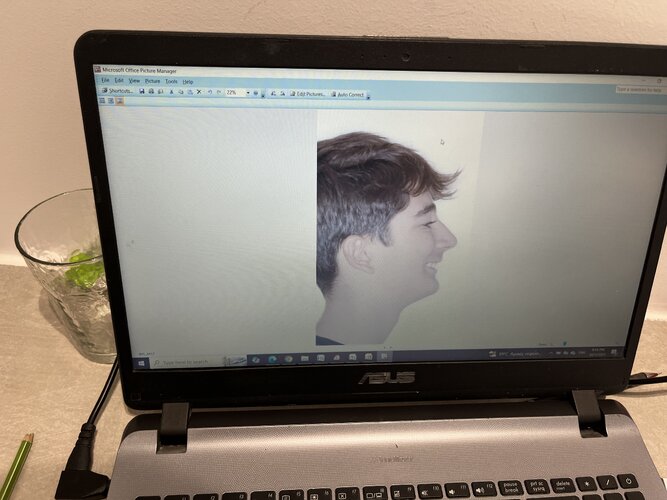

Important to note that my maxilla wasn’t downward grown until braces and headgear I am still 16 and upward thumb pressure is is not really doing anything much (I also had to fix my skeletal issue with my palate because my ortho only did tooth expansion instead of marpe/sarpe (aka breathing issues)